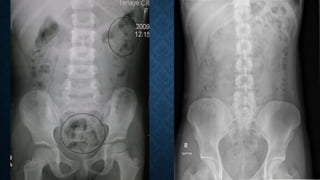

This document provides an overview of x-rays for medical students, covering topics such as ensuring x-rays are well-aligned, exposure levels, common artifacts and anatomical features, abdominal x-ray positions and views, and specialized x-rays including barium swallows, enemas, and tests to examine the esophagus, small bowel, biliary tree, and kidneys.